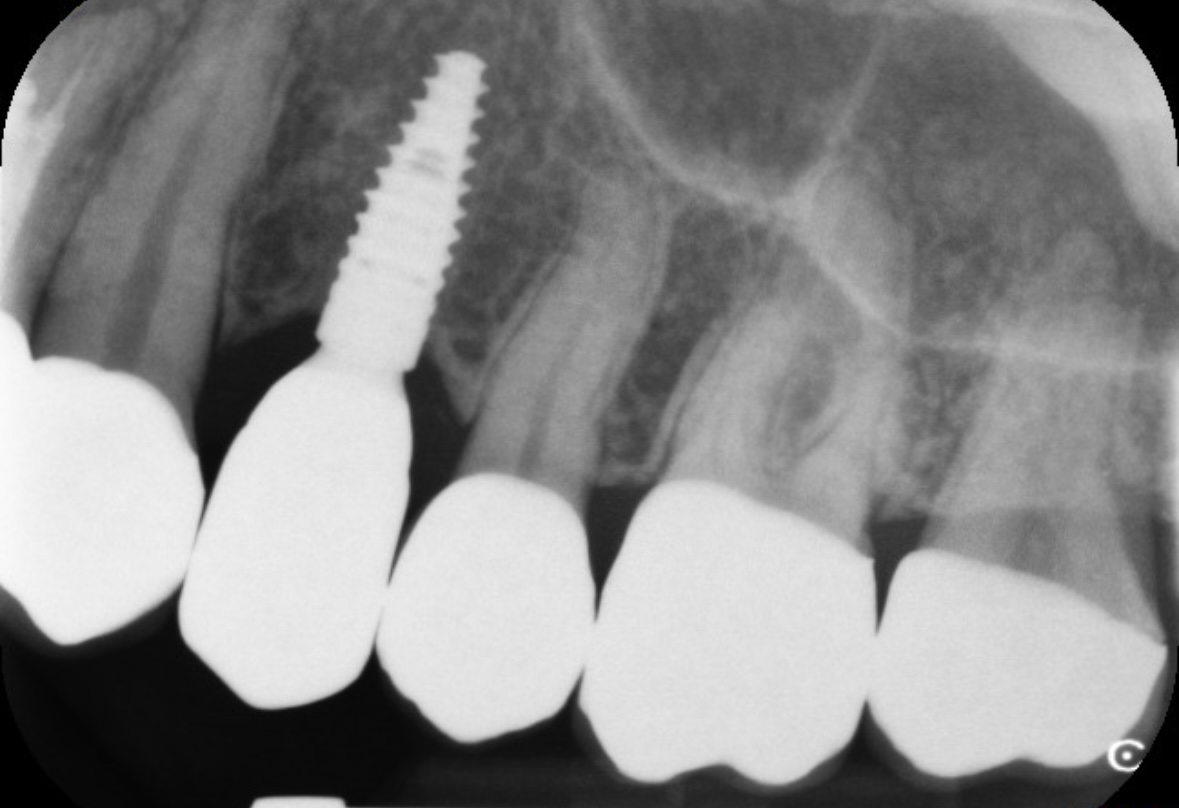

約1年前にインプラントを入れた歯の上に、フィステルのようなものができています。押すと痛みがあります。部分的なレントゲンを撮影しましたが、特に異常は見られませんとの事で治療をしてもらえませんでした。

同じようなできものは2か月ほど前にもでき、そのときは数日後に自然に消えました。しかし、今回また同じ場所にできてしまいました。なお、レントゲンを撮影したのは、このできものができる約5日前です。これは細菌による炎症なのでしょうか?

画像1IMG_0476.jpeg 画像2IMG_0474.jpeg

インプラントの部位の記入がなく隣の歯の状態も分からないのですが、

@ 近くの歯の根尖病変が原因で腫れてきている

A インプラント体に問題がある

B 歯周病

などが考えられますが、歯科用CT撮影が正確な診断に有効なこともあると思います